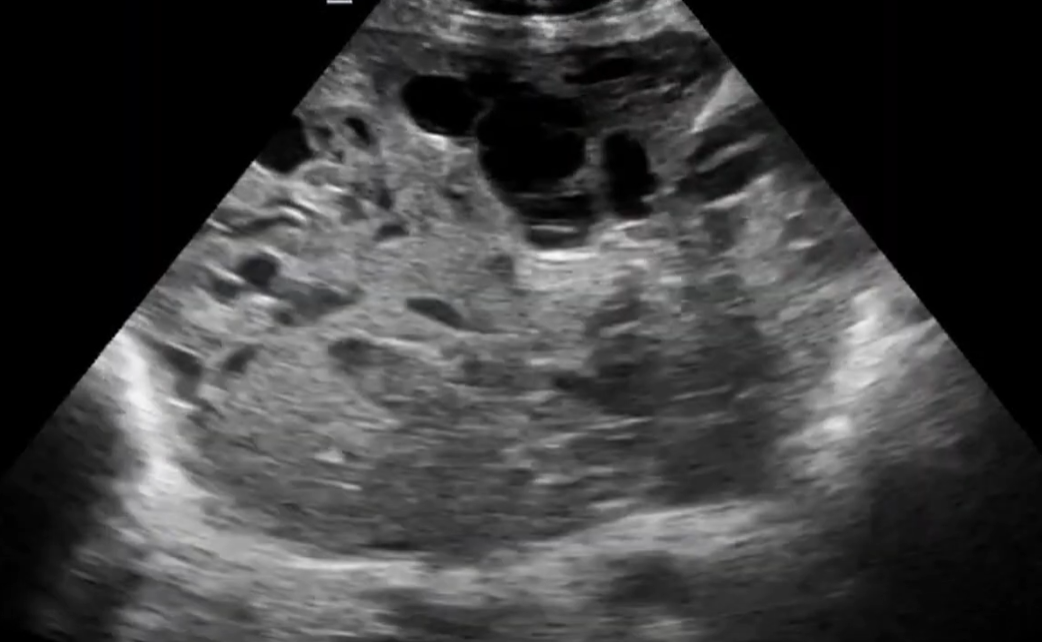

Loạn sản trung mô bánh nhau (Placental Mesenchymal Dysplasia - PMD)